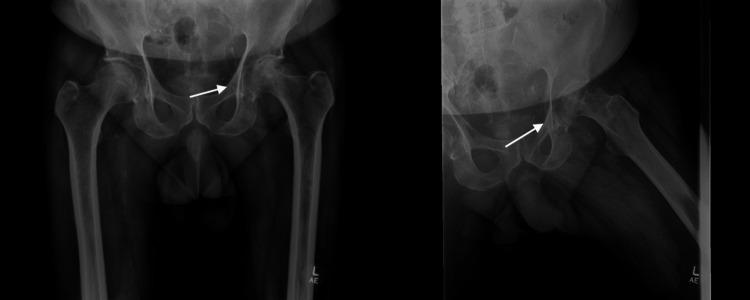

Avascular necrosis (AVN) of the femoral head results from disrupted blood flow that leads to bone tissue death. Nontraumatic risk factors include long-term corticosteroid use, excessive alcohol consumption, autoimmune diseases, and hematological disorders. Without an adequate blood supply, osteocytes die, causing microfractures that lead to structural collapse of the femoral head. Disruption of joint biomechanics causes hip or groin pain and limited range of motion (ROM). This case report presents a 56-year-old male patient with severe left hip pain and progressive functional decline over nine months. Imaging confirmed stage IV AVN with complete femoral head collapse. The patient failed initial conservative measures and underwent a cementless total hip arthroplasty (THA) augmented with peripheral screws in the acetabular cup. Post-operative recovery was unremarkable, with reported improvement of pain and increased hip motion at the six-week follow-up. This case highlights the importance of early diagnosis and treatment in advanced avascular necrosis of the femoral head. It also demonstrates the effectiveness of cementless total hip arthroplasty in providing good clinical outcomes.

摘要